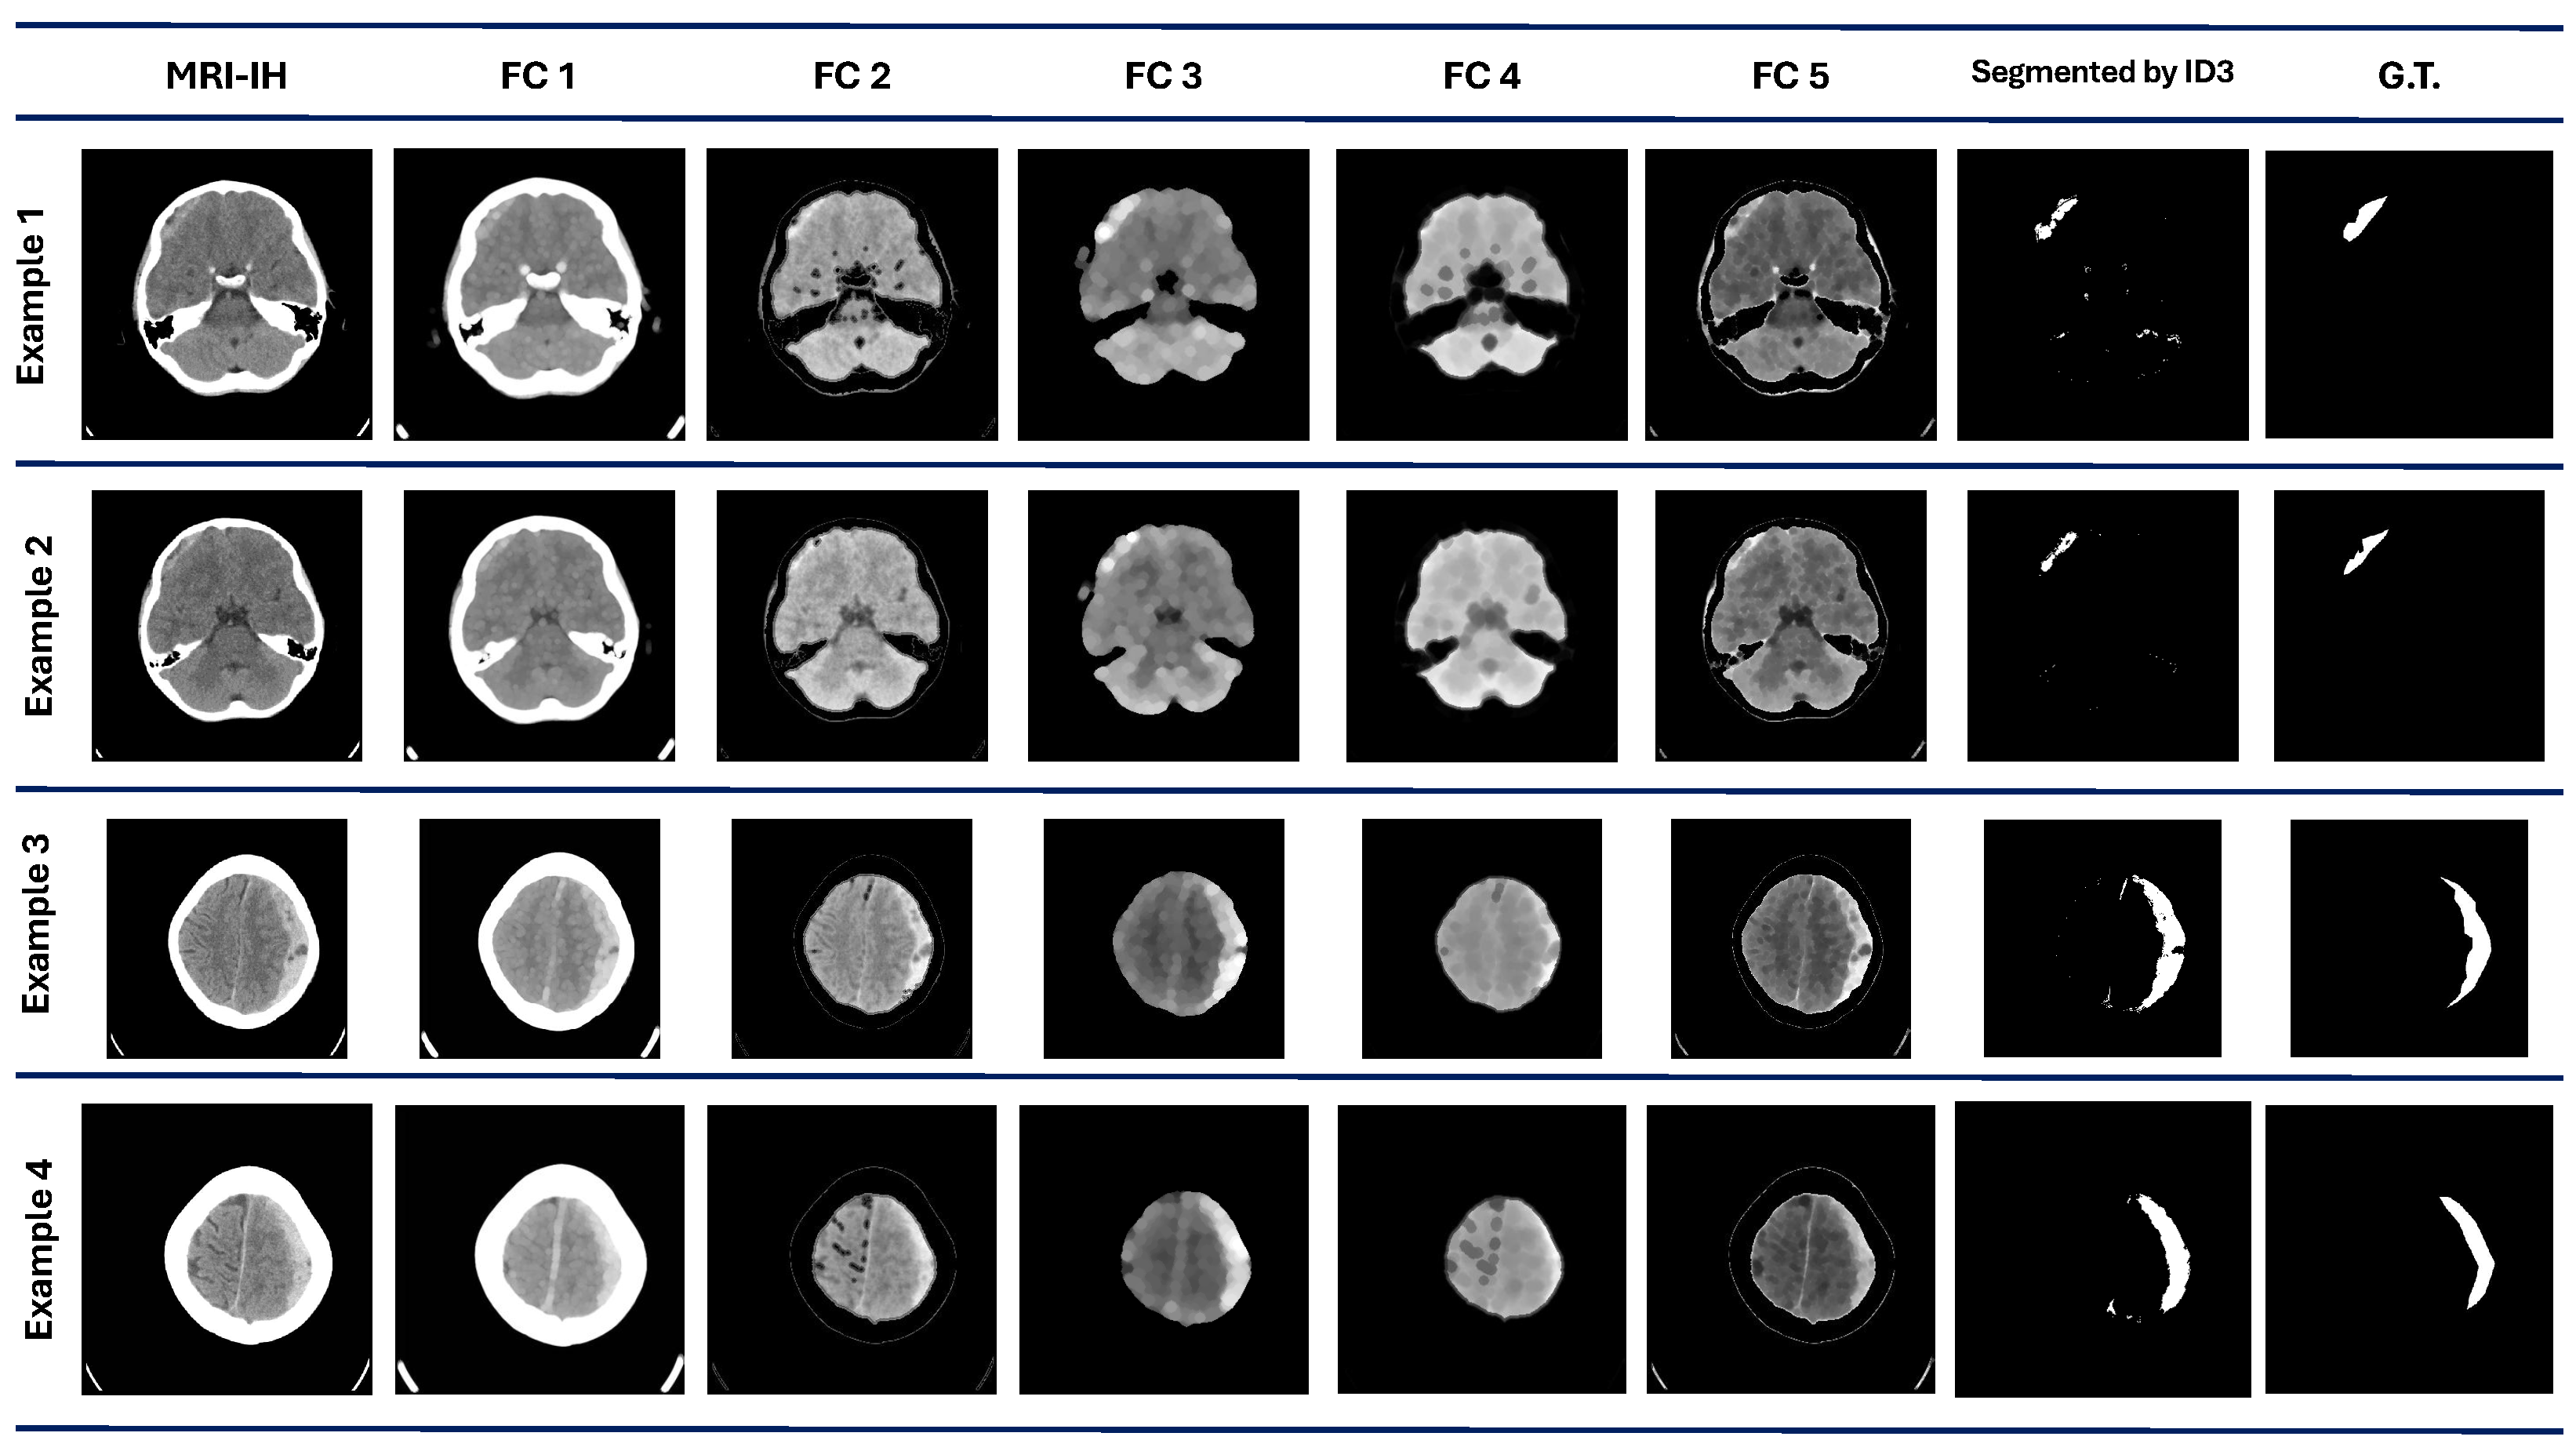

Figure 4 shows four examples of the results obtained from the five best individuals after the evolution process. The original image is also considered a feature for the pixel classification made by the ID3. , and are the image features constructed/extracted according to the individual, which contains the pipeline for the image processing.

Figure 4.

COVID-19 dataset results. The first column contains the original images. are the images processed by each best individual for each evolved population. The ID3 column contains the images segmented by the model at the pixel level. The G.T. column contains objective images.

We can observe that comparing qualitative results in Figure 4 with the quantitative performance with DICE in Table 3 demonstrates that the ROI is marked successfully in some cases, such as in examples 1 and 3. However, in examples 2 and 4, some regions are also marked as ROI even though they are not.